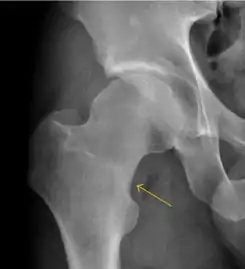

Slipped capital femoral epiphyses (SCFE)

Slipped capital femoral epiphyses (SCFE) usually affect 11- to 14-year-old adolescents (Figure 4). Radiographs may show widening and irregularity of the physis and posterior inferior displacement of the capital femoral epiphysis. On the AP view Klein’s line, tangent to the lateral aspect of the femoral neck, does not intersect the femoral head indicating that it is displaced. SCFE may compromise the blood supply to the femoral head and cause avascular necrosis, mainly when there is instability between the fragments.[1]